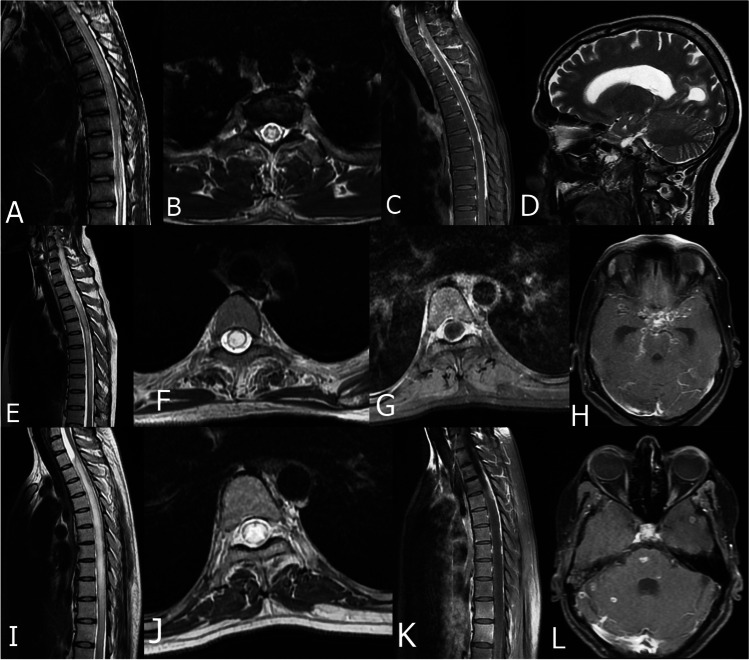

On neuroimaging, 17 (94.4%) patients were having an LETM. The cervico-dorsal spinal cord was the most commonly involved area, seen in 12 (66.7%). The myelitis extended to involve the area Postrema in 1 (5.6%) patient. Apart from myelitis, the MRI of the spine showed additional imaging features in these patients in the form of spinal meningeal enhancement 14 (77.8%), extra-axial collection 3 (16.7%), CSF loculation 3 (16.7%), arachnoiditis 3 (16.7%), and spinal tuberculoma 2(11.1%). MRI of the brain showed hydrocephalus 7 (38.9%), basal exudates 8 (44.4%), meningeal enhancement 11(61.1%), tuberculomas 9 (50%), and infarct 2 (11.1%) (Tables 1 and 2) (Fig. 2).

Fig. 2.

MRI of 3 patients with tuberculous myelitis. (A–D) Patient 1, sagittal T2 image showing LETM involving dorsal spine (A), Axial T2 image showing central hyperintensity within the spinal cord (B), post contrast sagittal image showing spinal meningeal enhancement (C), MRI brain of the same patient showing hydrocephalus. (E–H) Patient 2, (E) MRI spine, sagittal T2 image showing LETM involving cervico-dorsal spine, (F) axial T2 image showing myelitis involving the whole transverse diameter of the cord, (G) Post contrast axial image showing meningeal enhancement, (H) MRI brain of the same patient showing opto-chiasmatic tuberculomas. (I–L) Patient 3, (I) sagittal T2 image showing LETM with CSF loculation, (J) Axial T2 image showing myelitis involving the whole transverse diameter, (K) Post contrast image showing spinal meningeal enhancement, (L) MRI brain of the same patient showing multiple tuberculoma